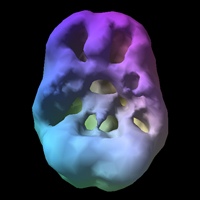

Wówczas pokazuję im skan mózgu SPECT. Badanie to ma na celu zobrazować ukrwienie fotografowanego organu.

- Zdjęcie drugie to mózg szesnastolatka, który od dwóch lat regularnie pali marihuanę.

Te puste miejsca nie są fizycznymi dziurami, do których można włożyć palec, ale są to miejsca niedokrwione. Taki stan mózgu bez wątpienia świadczy o jakiejś „utracie zdrowotnej”.

Marihuana uszkadza przede wszystkim płaty czołowe (umysł logiczny), które odpowiadają za nasze emocje, empatię, zachowania społeczne, organizację czy planowanie. Przykładowo długotrwałe palenie marihuany przekłada się na problemy z pamięcią nawet po jej odstawieniu. Niepokojące jest również to, że ten rejon mózgu odpowiedzialny jest za kontrolę zachowań, czyli również za abstynencję. Ujmując to metaforycznie „czym dalej w las, tym trudniej wrócić”.

Podczas moich warsztatów z młodzieżą pt. „Twój czas” zestawiam te dwa zdjęcia i zadaję pytanie „który mózg wybierasz?”

Wszyscy, i zwolennicy i przeciwnicy i ci, którzy nie mają zdania, odpowiadają „ten pierwszy”. To naturalne, że wszyscy chcemy być zdrowi i szczęśliwi. Jednakże ten mózg to mózg, na który trzeba sobie zapracować i pracować systematycznie, by utrzymać go w dobrej kondycji. Osoba paląca może „nie dźwignąć” takiego ciężaru, by uzyskać taki stan „umysłu”. Szczególnie kiedy zaczyna palić wcześnie. Okres nastoletni to okres bardzo progresywnego rozwoju i zmian zachodzących w mózgu. Niewłaściwe „używanie” tego organu może powodować konsekwencje na resztę życia. Palacz marihuany może „nie udźwignąć” wyzwania, by wykorzystać potencjał swojej pierwotnej natury, z którą przyszedł na świat. Może już nigdy nie wyćwiczyć tego najważniejszego „mięśnia”, od którego zależy jakość naszego życia.

Zdjęcia SPECT mózgu pochodzą https://www.amenclinics.com/